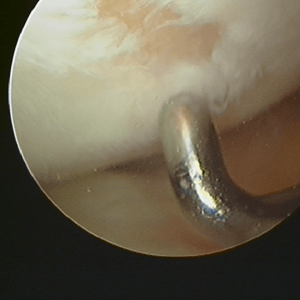

If the lining cartilage is damaged then you no longer have 2 smooth surfaces and using the knee joint can cause pain swelling and stiffness. While we cannot perfectly replace the cartilage that is damaged there are things that can be done to improve the joint after an injury to the cartilage. Firstly all loose or damaged cartilage can be removed and any loose flaps of cartilage can be trimmed so that they do not rub inside the knee or cause problems. Plugs of cartilage can be taken from one part of the knee and transferred to another using a device like an apple corer. The cartilage is taken from an area of the knee where it is not needed and placed where the knee is injured. This technique is called mosaicplasty or OATS (Osteochondralautograft transfer system).

Another way to bring new cartilage into a damaged area is to drill small holes in the bone. This causes bleeding at this site and the blood clot that forms brings new cartilage cells which can help heal the damaged area. This technique is called microfracture.